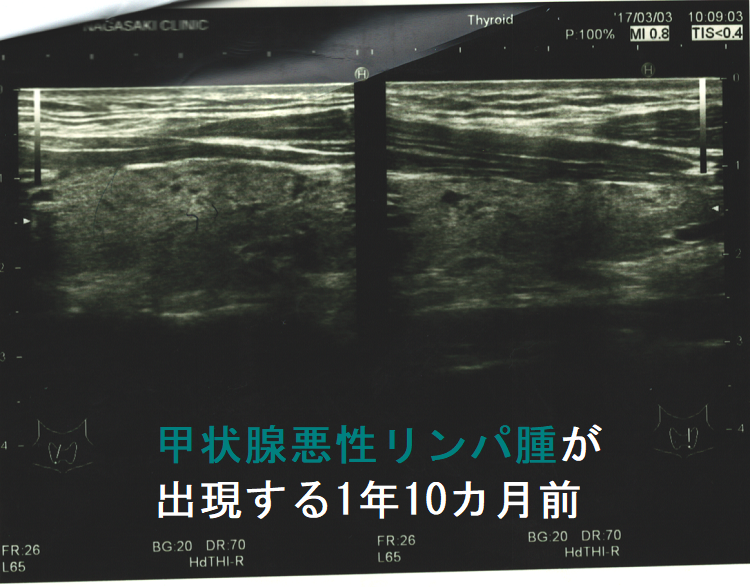

以下は長崎甲状腺クリニック(大阪)にて偶然から見つかった33歳男性の甲状腺悪性リンパ腫(命に係わる甲状腺癌)症例です。早期発見だったため、甲状腺全摘手術で完治し、5年以上経った今も長崎甲状腺クリニック(大阪)に通院されています。

もともと、奥さんの甲状腺機能低下症/橋本病を長崎甲状腺クリニック(大阪)で治療中。「一度、主人も診てやってください」の一言から、特に甲状腺の病気を疑うわけでないのに血液検査と甲状腺超音波エコー検査をおこなったところ甲状腺機能正常橋本病でした。この時(32歳時)は甲状腺悪性リンパ腫を疑う所見はなく、1年後の再診を指示しましたが、来院されたのは1年10か月後。 橋本病は甲状腺癌の発生母体であるため、当然のごとく甲状腺超音波エコー検査を施行。

(写真参照)右葉中部に18.5 x 13.2 x 8.8 mmの甲状腺悪性リンパ腫を認め、大阪市立大学(現、大阪公立大学) 内分泌外科(現在は業務統合のため廃止)にて根治的甲状腺全摘手術をおこない完治。発見が早かったため甲状腺から外に出ておらず、術後の抗がん剤も一切必要なく経過。5年以上経った今も元気に御夫婦で来院されています。もしも、甲状腺超音波エコー検査を行っていなければ、命を失っていた可能性大です。